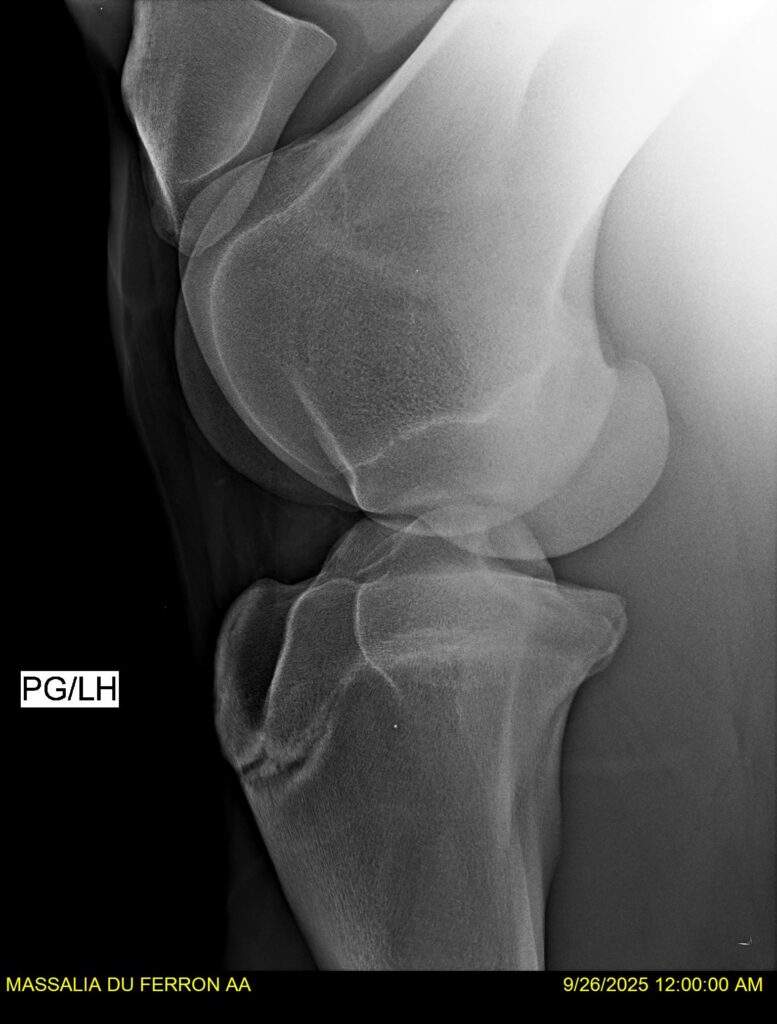

MASSALIA DU FERRON, jument qui prendra 4 ans par PRESTIGE KALONE x TRESOR DU RENOM. Un mental en or et un véritable sens de la barre ! Facile d’accès ! Bonne énergie et bons moyens. Souche moderne et très intéressante. Transport OK, maréchalerie OK, santé RAS, Bilan clichés radios OK.

RADIOS et COMPTE RENDU